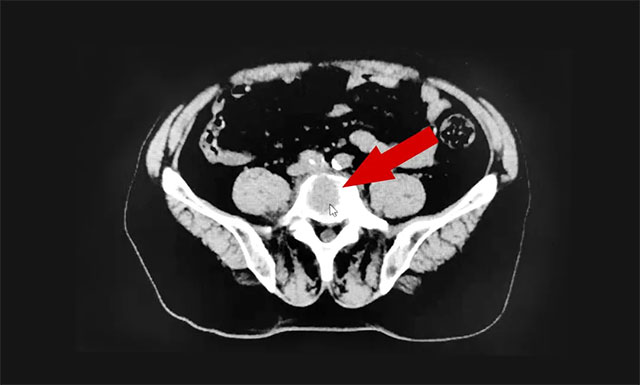

▲ 患者腰椎部出現(xiàn)轉移性骨腫瘤

年近六旬的患者黃先生(化名),于2019年發(fā)現(xiàn)肝臟腫瘤后進行了手術切除,術后病情有所好轉。然而好景不長,2020年,患者病情復發(fā),在外院行介入手術治療。此后,查出腰椎部出現(xiàn)轉移性病灶,持續(xù)性疼痛導致其夜間無法入睡,嚴重影響生活。今年1月下旬,患者來上海藍十字腦科醫(yī)院腫瘤(放療)科就治,希望通過放療減輕疼痛。